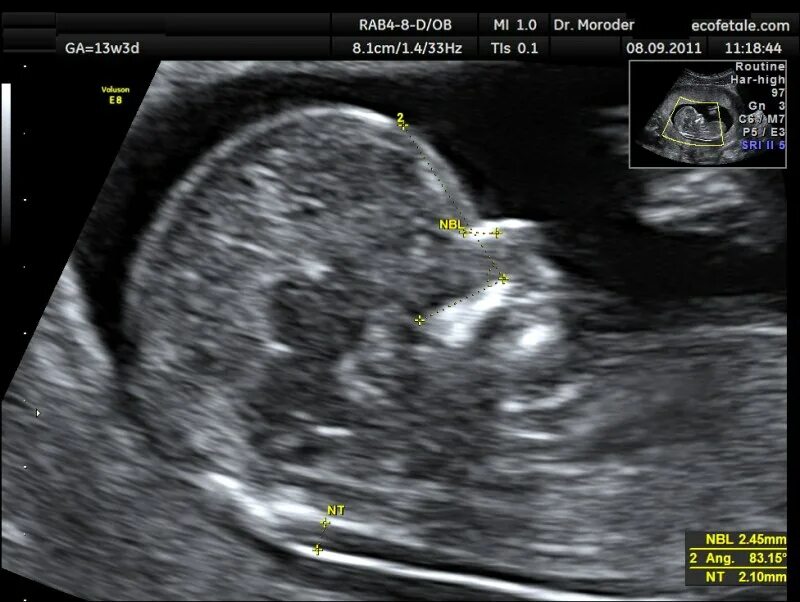

Воротниковое пространство 5